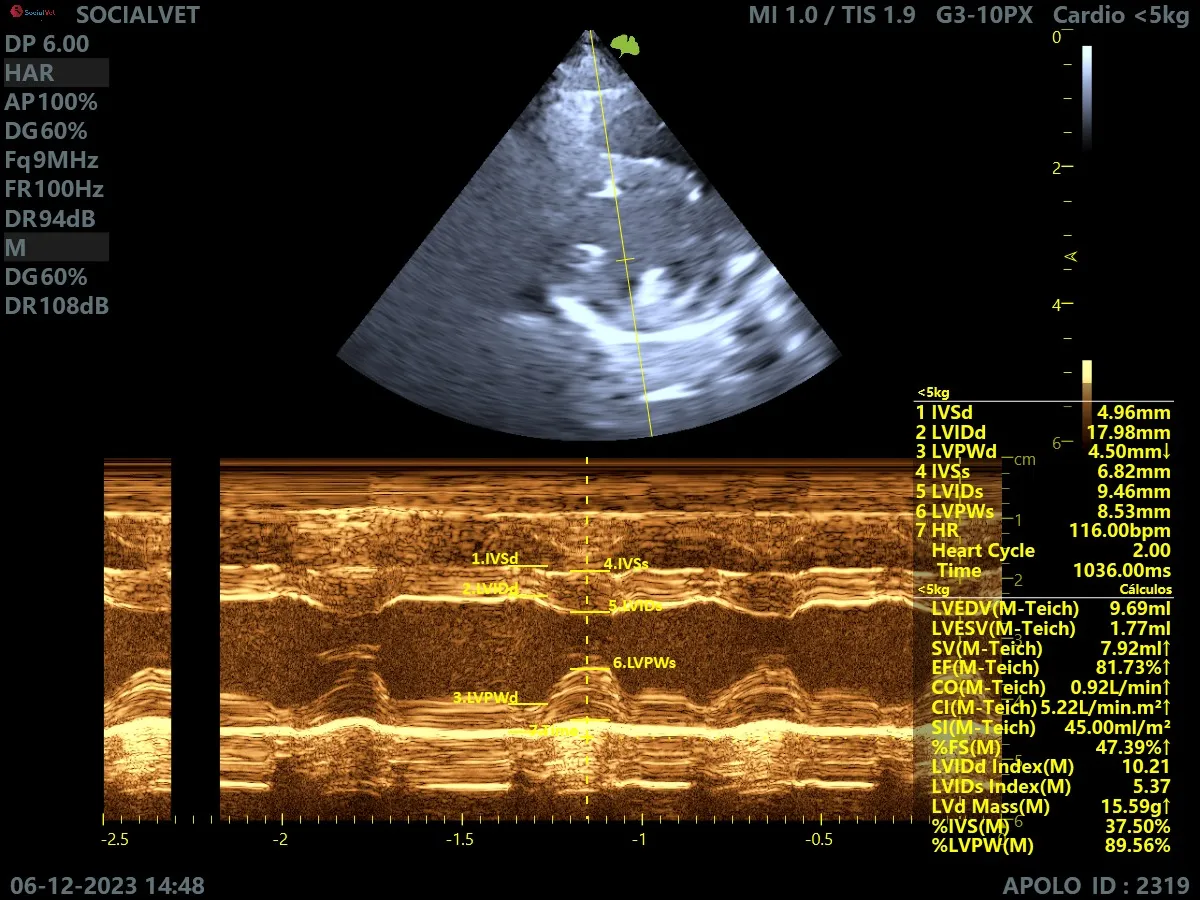

Cardiología Especializada

Diagnóstico y tratamiento de enfermedades cardíacas para asegurar una vida larga y saludable a tu mascota.

Ecografía y Eco-doppler

Tecnología de ultrasonido avanzada para un diagnóstico por imagen preciso y no invasivo.